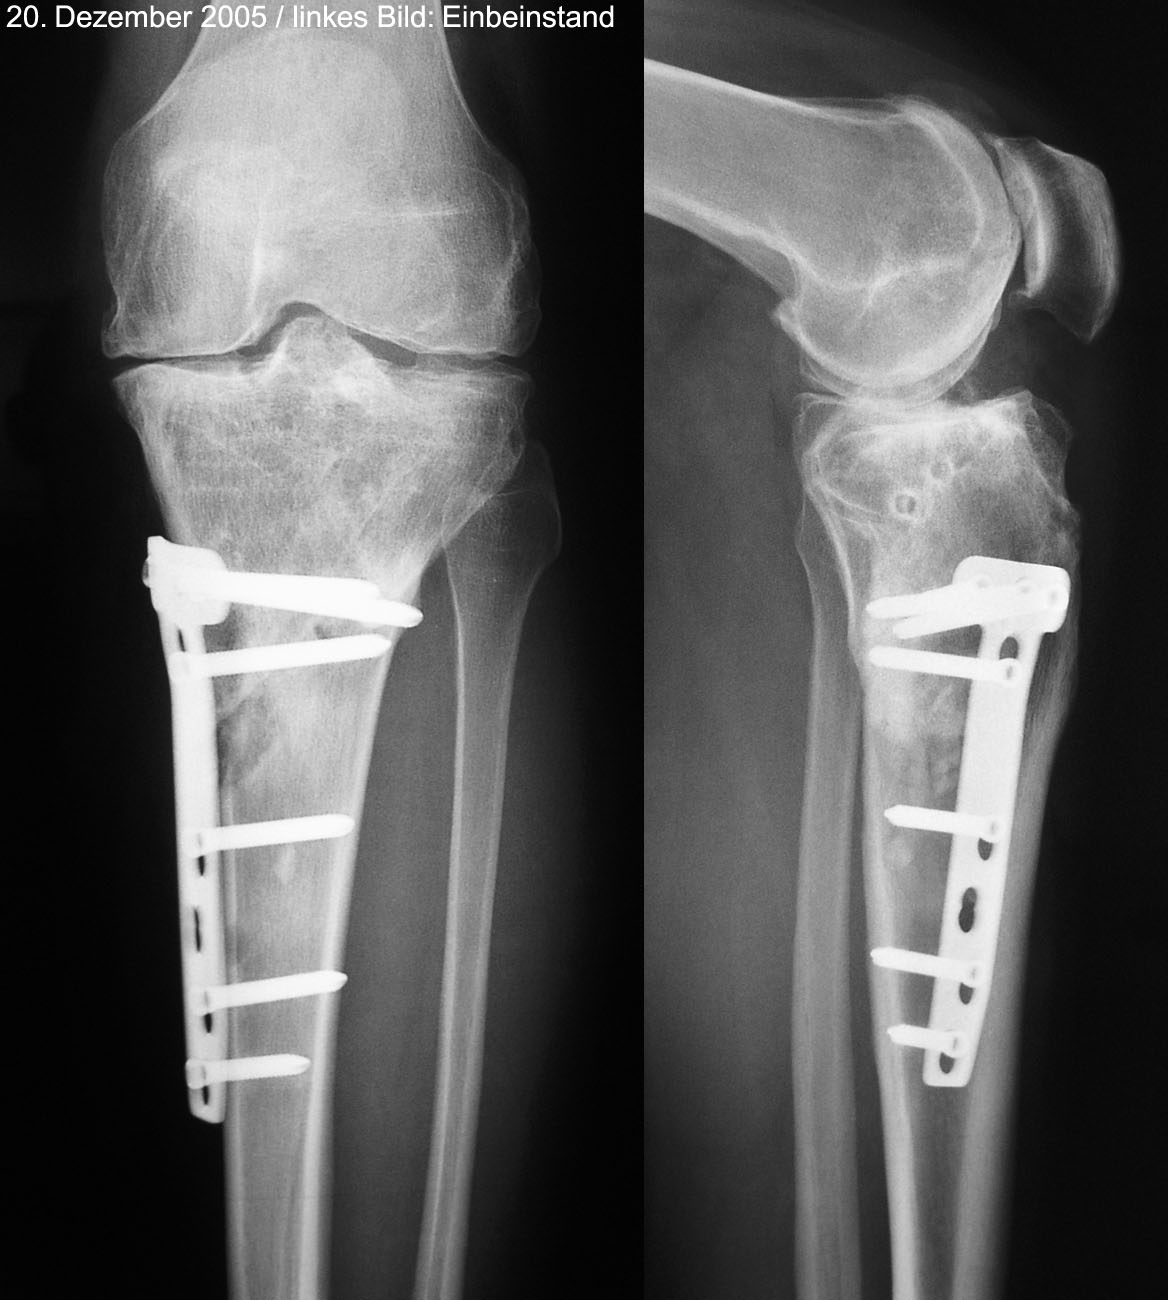

21. Dezember 2005

Paris, 17.12.2005 (Klicken für Vergrösserung)Lange Spaziergänge durch das weihnächtliche Paris erträgt mein Knie recht gut - mit den Schmerzen gehts in den letzten Tagen ganz sachte abwärts, immerhin. Auch velofahren geht wieder etwas besser. Aber bei besten Schneeverältnissen nicht auf der Piste zu sein mitten im Dezember - das bleibt schon gewöhnungsbedürftig. Auch die Röntgenkontrolle gestern im Salem brachte nicht viel Neues an den Tag: Mit dem Osteotomiespalt ist soweit alles OK, der ist schon fast kein Spalt mehr. Alles hält und heilt wie geplant. 20.12.2005: Das Öl ist da! (Klicken für Vergrösserung)Nur: Es wird weiterhin dringend vom Skifahren abgeraten. So werde ich die Weihnachtstage zum ersten Mal, seit ich denken kann, nicht skifahrend verbringen. Frust - besonders, weil heute Janica Kostelic mit ihrem lädierten Knie wieder mal einen Riesenslalom gewonnen hat. Ich versuche das ganze trotz allem Verdruss sportlich zu nehmen: Wieso nicht mal Schneeschuhwandern versuchen? Zudem hab ich endlich das in Seillans vor drei Wochen "gepflückte" Olivenöl in der Hand und kann damit während der Festtage feine Sachen kochen: Schmeckt vorzüglich - die Physiostunden auf dem Baum haben sich also gelohnt. Das aktuelle Röntgenbild ist hier abrufbar.